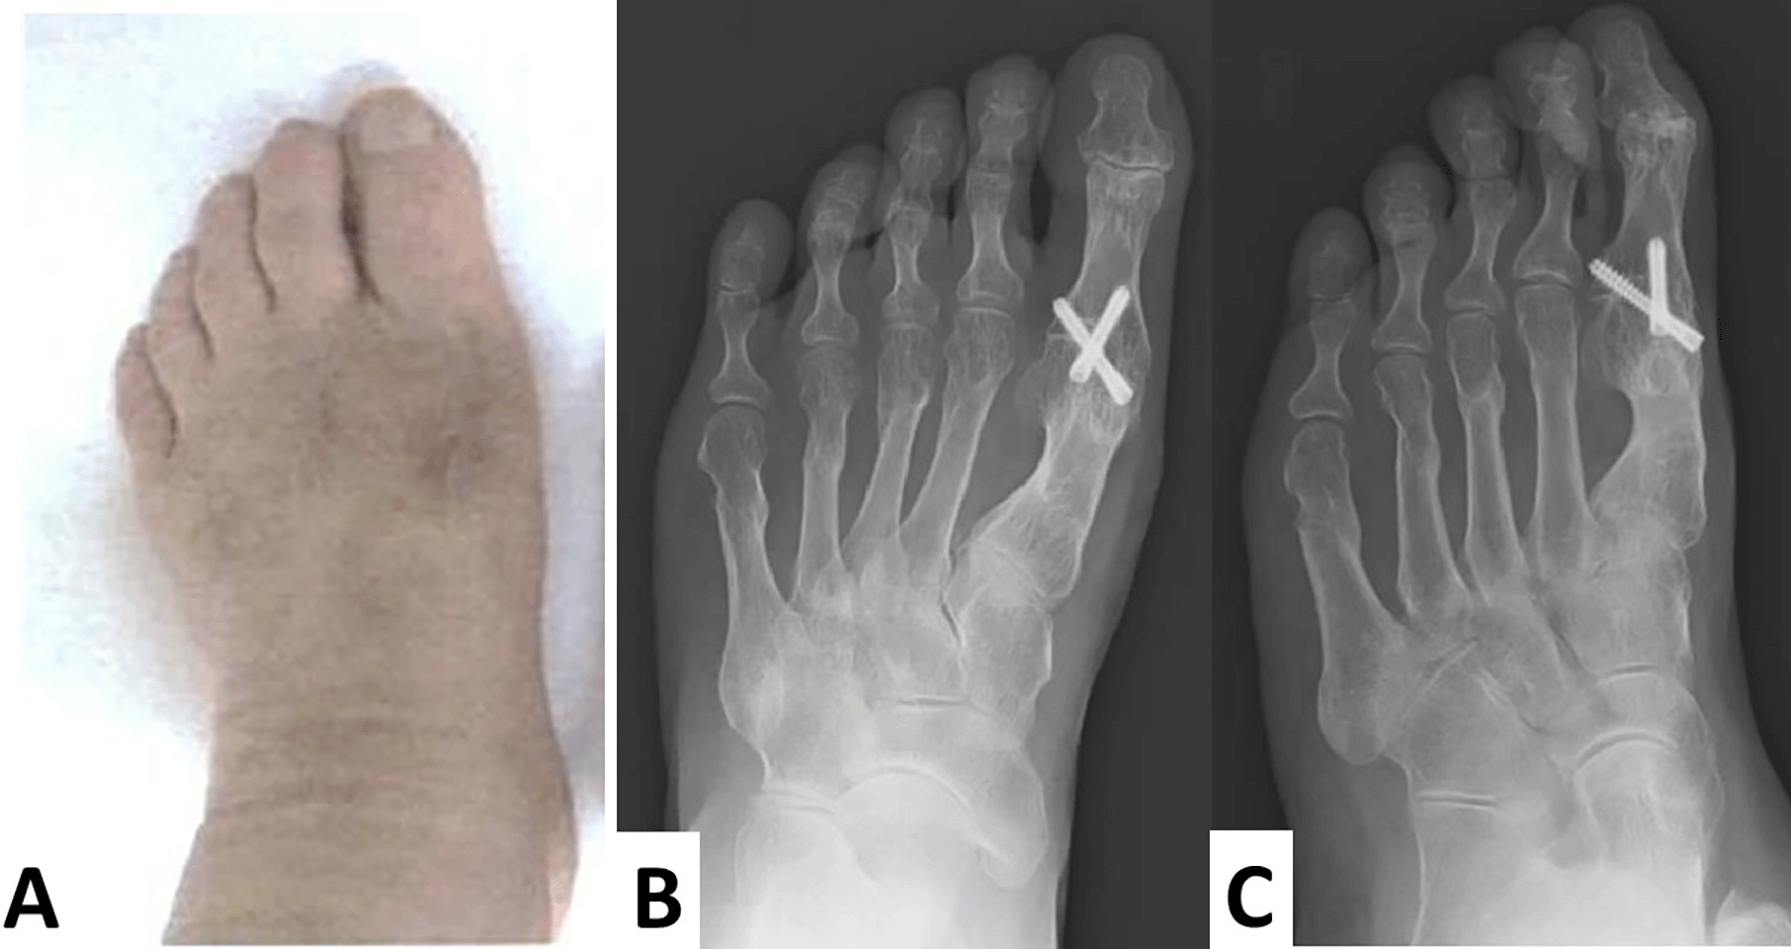

The screws remained intact and in place, and no valgus or varus deformities were apparent four years after surgery (Figure 6A–C).

No recurrence of hallux varus and hallux valgus is observed (A). The screws are intact, in place, and no valgus or varus deformities are apparent. Additionally, each osteotomized lesser toe is united (B, anteroposterior view; C, oblique view).

Post-operative evaluation of the JSSF score of hallucis was 81 out of 100 (pain, 30 out of 30; deformity, 23 out of 30; range of motion, 5 out of 15; gait, 20 out of 20; and activity of daily life, 3 out of 10), which showed a six-point increase. A six-point increase in deformity and a 10-point increase in walking abilities were noted; however, a 10-point decrease in range of motion was observed. No deformities were apparent and pain that worsened during movement was relieved.